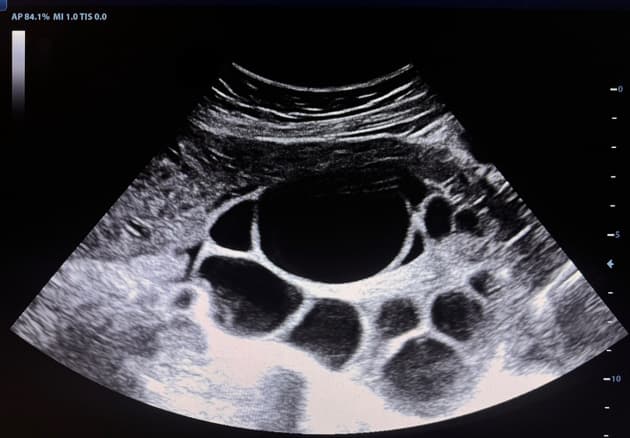

- Ở phần phụ phải, có buồng trứng thai với túi noãn hoàng và cuống phôi.

- Hoạt động tim phôi trong khoảng 128-133 lần/phút.

- Trên các chuỗi hình ảnh động (cine loops) có ép, buồng trứng thai tách biệt rõ ràng với buồng trứng phải.

- Ngoài ra, các hình ảnh có ép cho thấy rõ ràng thai ngoài tử cung là cấu trúc riêng biệt, tách biệt hoàn toàn với buồng trứng.

Chửa ngoài tử cung vòi trứng (tubal ectopic pregnancy)

- "Sự hiện diện của túi noãn hoàng, cuống phôi và hoạt động tim phôi bên ngoài tử cung xác nhận chửa ngoài tử cung còn sống."